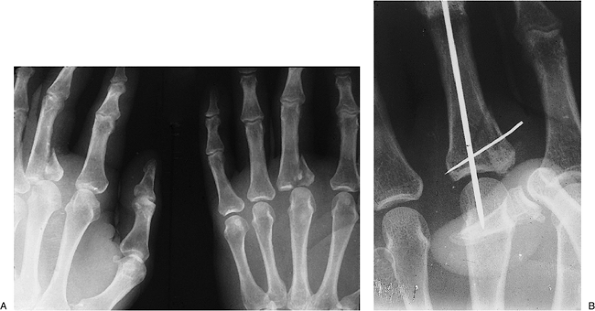

Figure 9-14 shows a patient with significant displacement of fractures of the neck of the metacarpals of the little and ring fingers.

-

Some surgeons would suggest that open reduction and internal fixation is indicated.

Closed reduction would no doubt be difficult, if not impossible.

Figure 9-17 shows such an injury to the base of the little finger metacarpal and an associated fracture of the ring finger metacarpal.

Treatment was by open reduction and

K-wire fixation of the CMC dislocation, with parallel K-wires across

the ring finger metacarpal fracture.

Figure 9-17 CMC joint dislocation of the little finger and fracture of the ring finger metacarpal. A, B.

X-ray appearance of the injury. Note the CMC dorsal dislocation of the

little finger metacarpal and fracture of the ring finger metacarpal.

Note also that the oblique view is more revealing than the AP view. C, D. Postoperative appearance showing anatomic reduction and fixation with K-wires. Note the bent ends of the K-wires (see text). -